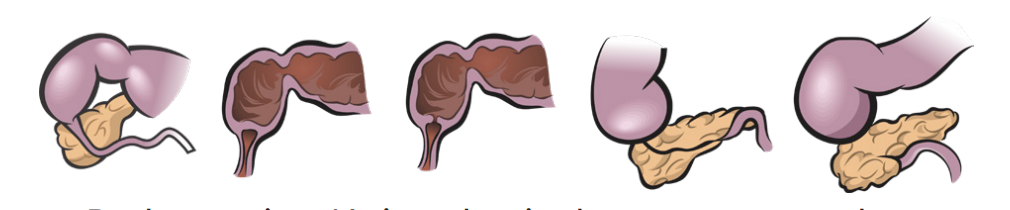

A classificação de Gross detalhada

Embora o Tipo C (86,6%) — atresia proximal com fístula distal — seja o mais comum, entenda a implicação clínica dos outros:

- Tipo A (7,5% – Long Gap): Sem fístula. O abdome é escavado (sem gás). O desafio aqui é a distância entre os cotos.

- Tipo E (3,8%): Fístula em H. Não há atresia, apenas a comunicação. O diagnóstico é tardio, muitas vezes por pneumonias de repetição.